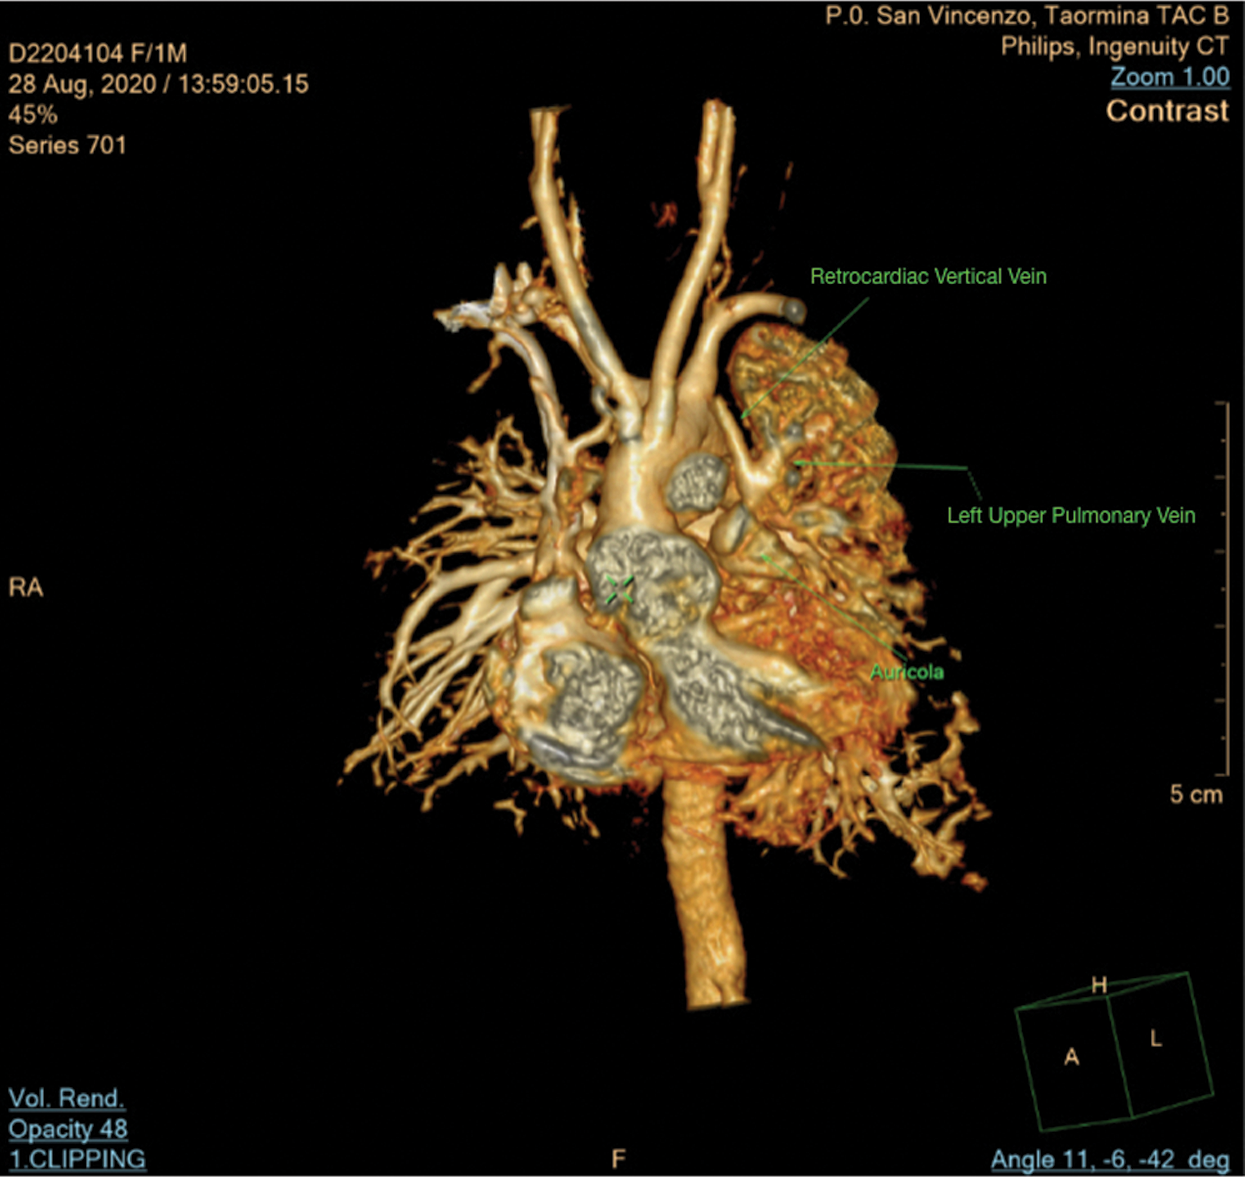

On the sixth day post-surgery, due to inability for ventilatory and inotropic support weaning, added to presence of abnormal blood flow at retrocardiac level seen in echocardiography images, it was decided to perform CT scan that demonstrated APVC: A left upper pulmonary vein draining into a retrocardiac vertical vein (Fig. 6). A new surgical procedure needed to establish correct anatomy left upper pulmonary vein draining into a retrocardiac vertical vein was identified and then anastomosed to the left atrial posterior wall. Patient returned to ICU and was discharged after complete recovery and without any complications.

Figure 6: Computed tomography scan shows left upper pulmonary vein draining in retrocardiac vertical vein